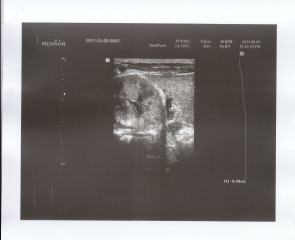

سونوگرافی کلیه و مجاری ادراری (10/2/90) :کلیه ها ابعاد طبیعی راست=45

mm

و و چپ=46mmدرضخامت

پارانشیمال طبیعی داشت.شواهدی به نفع سنگ یا ضایعه فضاگیر نداشت. ولی قطر لگنچه

در کلیه چپ 32 میلیمتر

AP

می باشد که نشان دهنده

mild stasis

است.

شواهدی بنفع هیدرونفروز در کلیه راست دیده نمی شود.